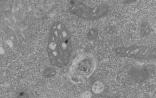

厦大韩家淮教授Cell Res解析细胞焦亡

8月30日,国际知名学术期刊Cell Research在线发表了厦门大学生科院韩家淮教授课题组的最新研究成果。